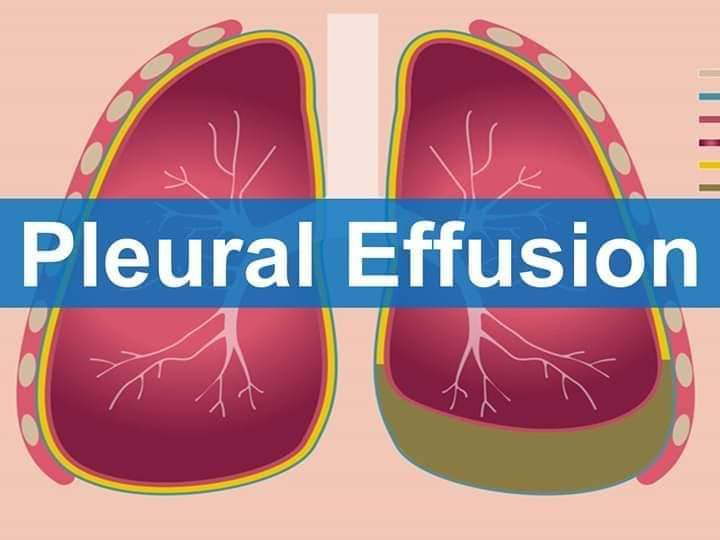

Pleural effusion, sometimes referred to as “water on the lungs,” is the build-up of excess fluid between the layers of the pleura outside the lungs. The pleura are thin membranes that line the lungs and the inside of the chest cavity and act to lubricate and facilitate breathing.Dec 18, 2018

Listen to pronunciation. (PLOOR-ul eh-FYOO-zhun) An abnormal collection of fluid between the thin layers of tissue (pleura) lining the lung and the wall of the chest cavity.

During pleural effusion, excess fluid accumulates in this space due to increased fluid production or decreased fluid absorption. Common causes of pleural effusion include congestive heart failure, kidney failure, pulmonary embolism, trauma, or infection.Jun 26, 2017

Pleural effusion is excess fluid that accumulates in the pleural cavity, the fluid-filled space that surrounds the lungs. This excess can impair breathing by limiting the expansion of the lungs. Various kinds of pleural effusion, depending on the nature of the fluid and what caused its entry into the pleural space, are hydrothorax (serous fluid), ...